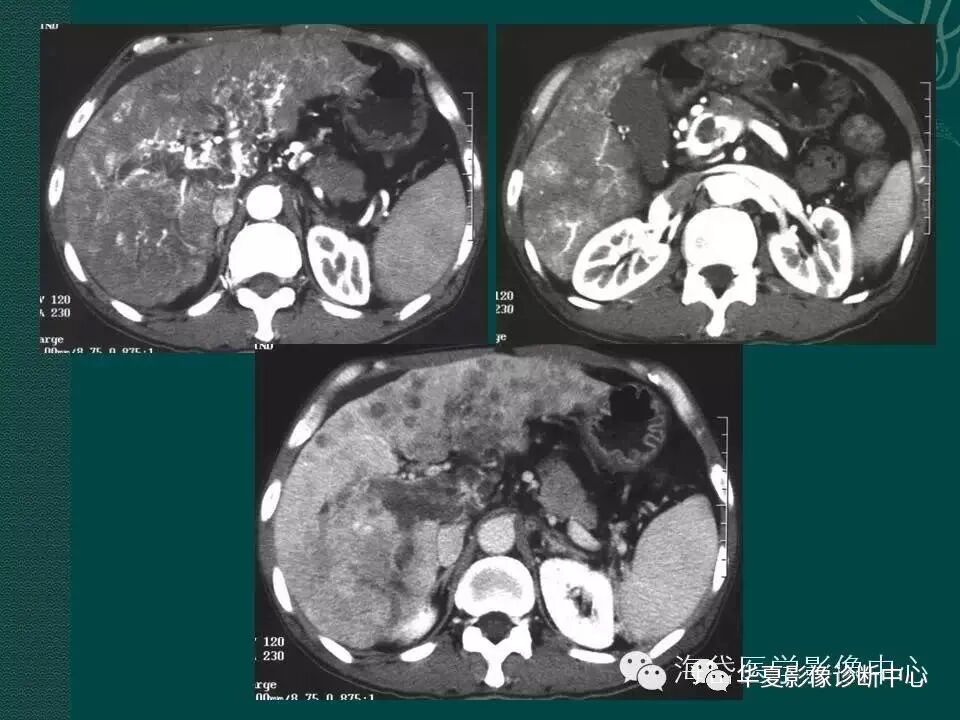

图1 门静脉主干及分支血栓伴侧枝血管建立

图2 门静脉血栓伴广泛侧枝循环建立